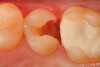

Fig 1. A preoperative occlusal view of tooth No. 13 that has a “stain” in the occlusal groove that does not “stick” with an explorer.

Figure 1

Fig 2. After a fissurotomy bur is used to conservatively open into the groove, a rather extensive carious area is discovered.

Figure 2